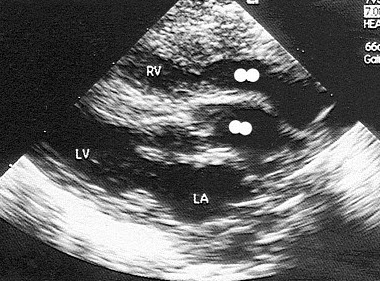

16、单项选择题

该病例最可能的诊断()

A.矫正型大动脉转位

B.右室双出口

C.完全性大动脉转位

D.主动脉骑跨

E.单心室